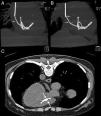

No internamento apresentava‐se em regular estado geral, hipocorada (3+/4+), apirética e pesando 65,5kg. O exame dos pulmões não revelou anormalidades; a pressão arterial era de 110/60mmHg e a frequência cardíaca de 108bpm; sons cardíacos normais e rítmicas com sopro sistólico discreto na região paraesternal direita, sem irradiação. No abdômen não havia visceromegalias palpáveis. As extremidades estavam bem perfundidas e sem edemas. Exames laboratoriais iniciais mostraram queda da hemoglobina, não justificada por perdas gastrointestinais ou ginecológicas, com hematócrito 22%, hemoglobina 7g/dL, VGM 93fL, CMHG 32%, leucócitos 2,7x103/mm3 (neutrófilos 64%, eosinófilos 3%, linfócitos 24%, monócitos 8%) e plaquetas 238x103/mm3. A creatinina (2,1mg/dL) e a ureia (73mg/dL) estavam aumentadas, com os eletrólitos normais; a proteína C reativa (6,8mg/dL) e a ferritina (1.043μg/L) também estavam elevadas. O tempo de protrombina (13,4 segundos), atividade protrombínica (81,9%) e INR (1,14) estavam normais. A urinálise não mostrou alterações significativas e a urocultura foi negativa. Hemoculturas (três amostras) demonstraram o crescimento de B. cepacia sensível apenas a meropenem e a trimetoprim (TMP) com sulfametoxazol (SMZ). Esta associação foi administrada por via endovenosa (TMP 160mg e SMZ 800mg a cada 12 horas). A radiografia de tórax foi normal, mas o ecocardiograma transesofágico revelou a presença de corpo estranho no átrio e ventrículo direitos. A tomografia computadorizada de tórax demonstrou imagem densa e alongada estendendo‐se do átrio direito através da válvula tricúspide até o ventrículo direito, com dobras e emaranhados na cavidade ventricular (Figura 1 A e 1B). Em virtude do posicionamento defeituoso e suspeita de fragmentação o cateter foi retirado por via percutânea; mas a tomografia de controle mostrou uma imagem intracardíaca densa (Figura 1C). Outros procedimentos menos invasivos não foram adotados, pois o fragmento parecia aderido à parede da cavidade em virtude de sua longa permanência, o que propiciaria a origem de êmbolos. No 16.° dia de antibioticoterapia foi realizada cardiotomia, que confirmou a presença de um fragmento do cateter fortemente aderido ao endocárdio. O pós‐operatório decorreu sem intercorrências. A paciente evoluiu com normalização do hemograma e manutenção da função renal e a alta hospitalar ocorreu no 17.° dia do pós‐operatório. O uso do antibiótico foi mantido por via oral mais quatro semanas e ela permanece assintomática em acompanhamento ambulatorial.

Estudo tomográfico do tórax. A e B: imagem densa e alongada estendendo‐se do átrio ao ventrículo direito, com dobras e emaranhados na cavidade ventricular, além de aspecto sugestivo de fragmentação (setas). C: exame de controle após a retirada do cateter, evidenciando imagem compatível com fragmento intracardíaco (setas).